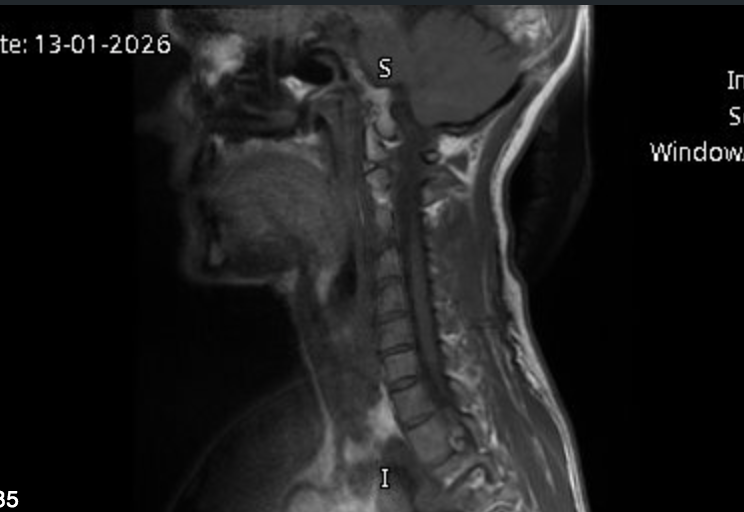

Within 20 minutes an MRI scan showed a detailed image of my neck, confirming a herniated disc and the cause of the pain I was feeling. I was able to get a self-funded scan within a week via referral from my osteopath.

However this scan doesn’t show fascia, and the tension I know is present in the front of my body, and the likely cause of the strain on my neck. In fact “the cause” wasn’t really discussed, other than a symptom of my age. Treatment offered was physiotherapy once out of pain, or possible surgery. Osteopathy and Myofascial Release were dismissed, although the GP hadn’t even heard of the latter.